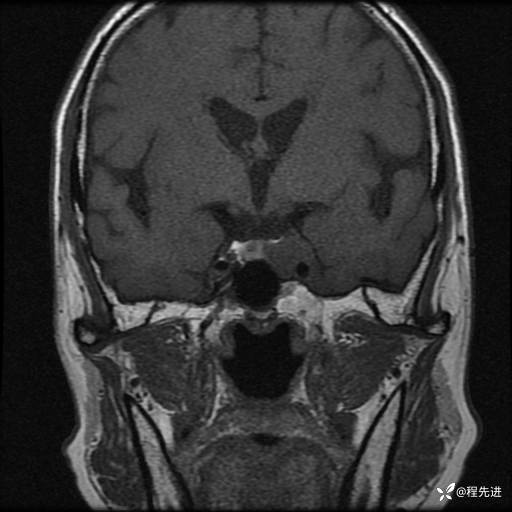

患者性别:男

患者年龄:74岁

简要病史:出现视物重影2月余,未予重视,2月来症状逐渐加重

MRI平扫+增强:

T2: